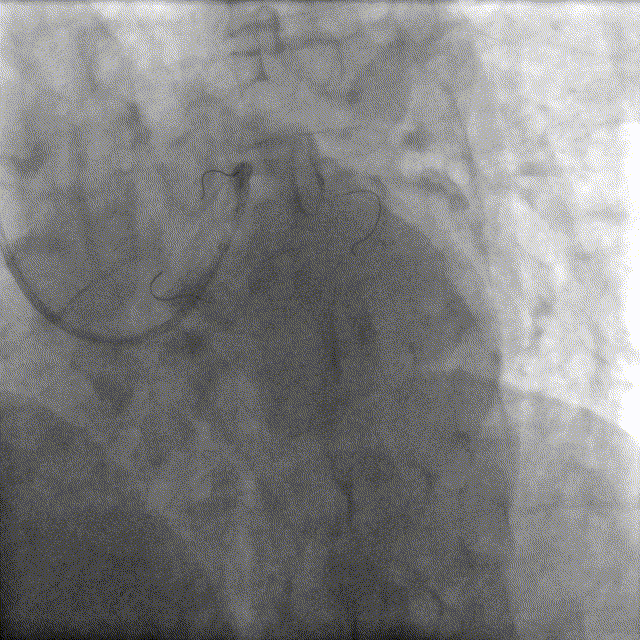

造影如下

患者左主干前三叉1,0,1型病变,主干末端偏心40%狭窄;前降支病变自开口延续至中段,口部80%狭窄,中段80%狭窄,病变位置钙化严重;回旋支近段约30%轻度狭窄,第一及第二钝缘支开口80%局限病变。

分析该造影结果

1.左前降支病变适宜PCI治疗,三叉虽为101病变但主干偏心狭窄,管腔狭窄程度有限,三叉位置策略采用精确定位前降支开口还是单支架跨越(CrossOver)方式,可先以IVUS精确测量主干管腔面积指导选择。

2.回旋支口部管腔未见严重病变且发出角度大,故可采用导丝保护策略,以简化手术过程。

3.前降支系钙化病变,预处理需采取针对钙化斑块的消蚀或碎裂策略。钙化病变较长,旋磨碎屑量大,慢血流风险高,且旋磨过程分支不可保护,如出现回旋支开口夹层则补救处理迟滞。另外,左右头位可见主干与前降支成角较大,且病变位置血管僵硬,故而旋磨穿孔风险很大。因此,该例决定采用冲击波球囊碎裂钙化,冲击波可在安全穿过软组织同时碎裂浅层和深层钙化。